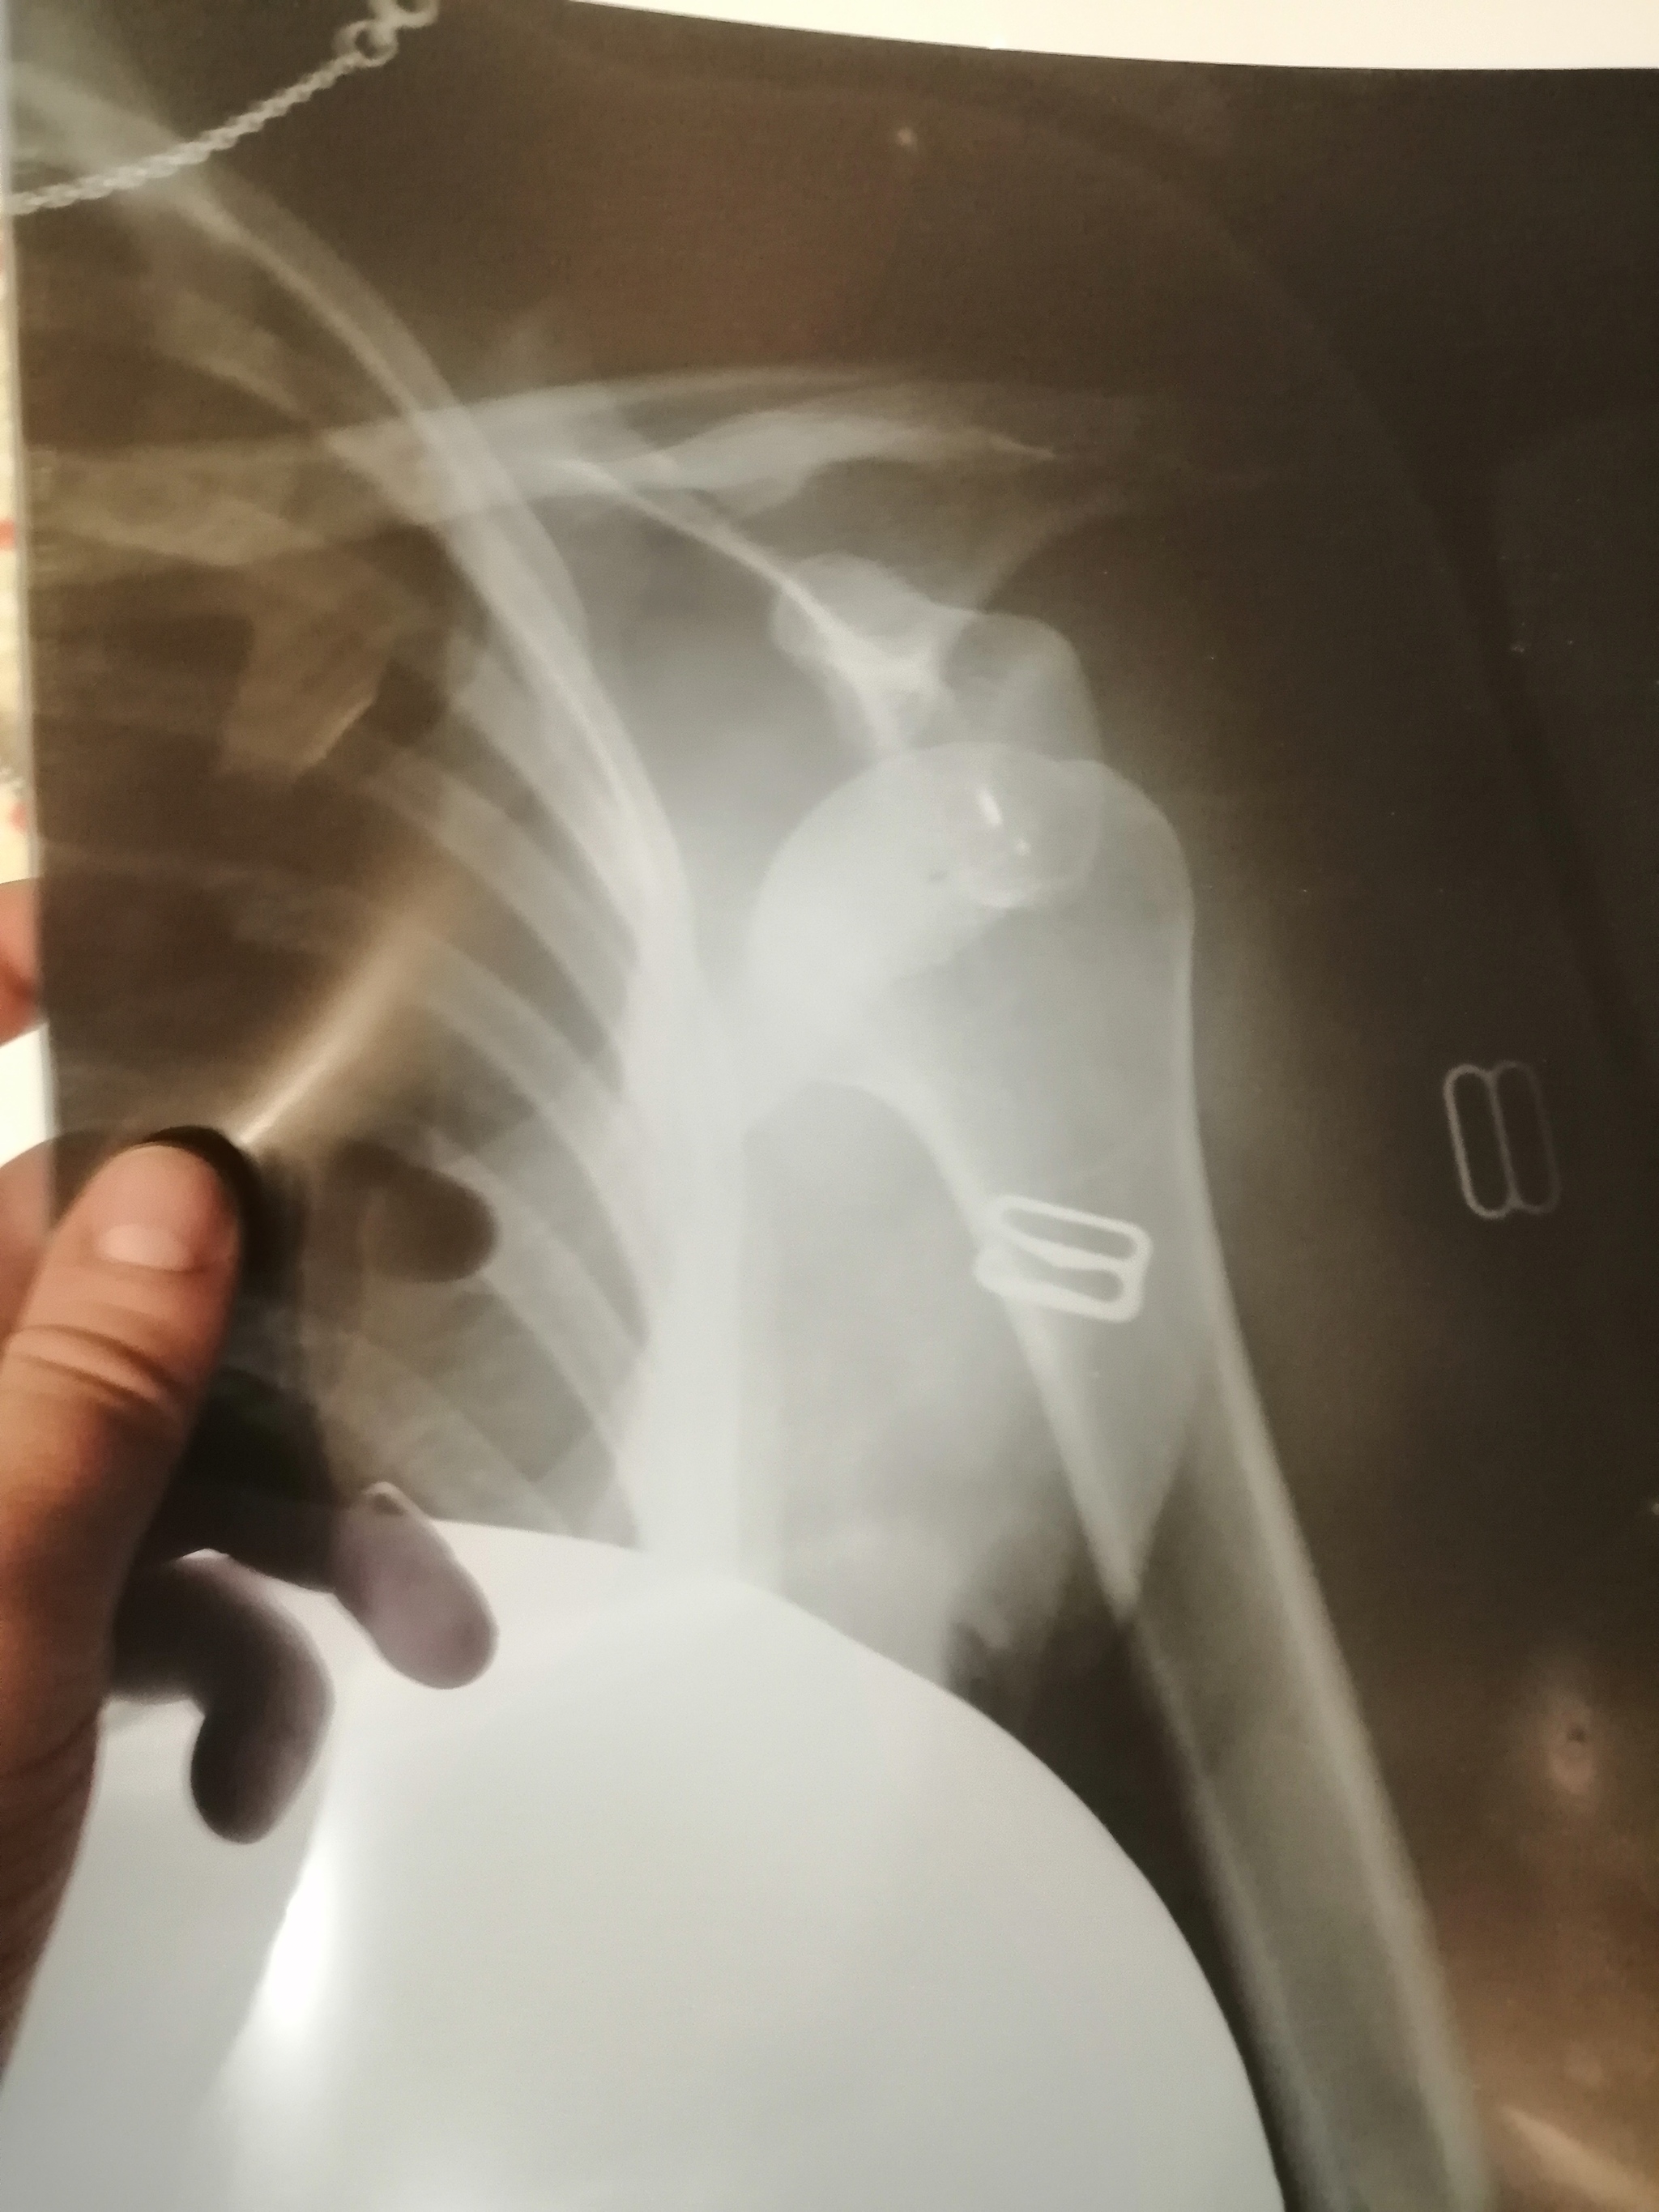

Вчера решили съездить покататься на плюшках, поехали на большую горку, специально оборудованную для покатушек, с прокатом и лесенками для подъёма. Напоследок отправили жену и тут все пошло не так, на кочке её перевернуло, и она выпала из плюхи. Как же она летела.. Я думал ничего целого от неё не осталось. Но все вроде обошлось, кроме плеча... Мигом рванули в больницу, сделали снимок, вывих плеча.. Кость почти к ребру ушла..

В итоге сказали сложный вывих. Врач сказал, ещё немного и пришлось бы ставить пластину и реабилитация плеча была бы 3 года.

А пока ходим в гипсе, реабилитация плеча 3 недели.